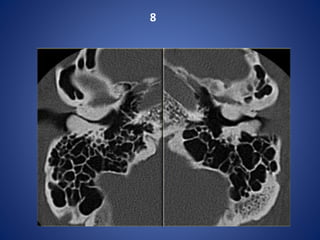

Dehiscent jugular bulb